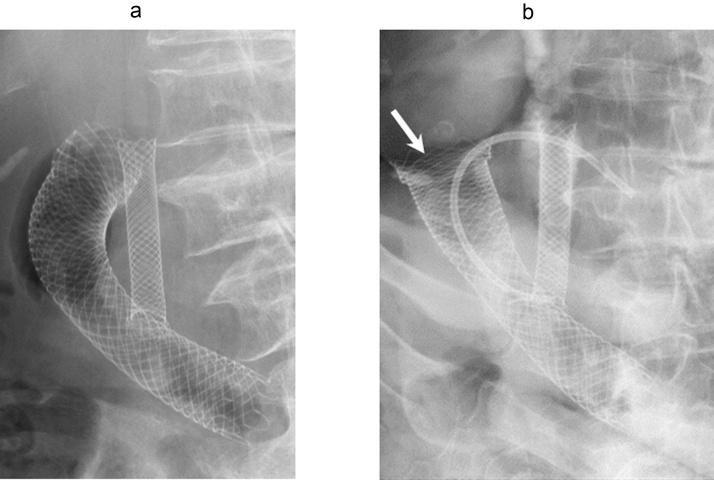

An 80-year-old woman suffering from stenosis caused by advanced periampullary cancer underwent metallic stent placement and her symptoms improved. While attempting biliary re-stenting to prevent restenosis after 4 months, the proximal end of the duodenal metallic stent migrated into the abdominal cavity. Using a laparotomy intraoperative endoscope, duodenal stents were placed into the prolapsed stent in the form of stent-in-stent to reduce the axial force of the stent, after which the puncture site was closed by suturing. No leakage or stenosis was observed at the duodenum, and the patient was able to eat normally until her death 4 months after surgery.

Surgical closure following intraoperative endoscopic additional stenting is a viable option for duodenal perforation caused by a stent.